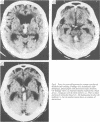

The clinical and computerised tomographic findings in 40 patients with primary pontine haemorrhage were reviewed. Twenty-nine patients were hypertensive. Four patients had angiographic or necropsy evidence of vascular malformations. In 33 cases, there was rapid deterioration to maximal neurological deficit; whereas in seven cases, there was sudden onset but subsequent progression to maximal deficit 24 hours to 5 days following the initial ictus. Seven patients had clinical features considered atypical for pontine haemorrhage. Five patients survived and four of these were capable of performing activities of daily living within 3 months of the haemorrhage. In all cases CT showed a hyperdense non-enhancing brain stem haematoma. There was evidence of ventricular extension in 27 cases. There was CT evidence of subarachnoid blood in only two patients who also had vascular malformations. In 26 cases, there was CT evidence that the haematoma extended to the midbrain and in four cases to the thalamic region. In six cases CT was repeated 6 to 21 days after the initial scan and it showed resolution of the haematoma in size and density; none of the haematomas showed post-contrast enhancement on initial or follow-up CT.